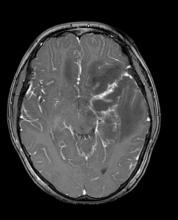

Acute post-surgical pneumocephalus is frequent in patients with cranioencephalic pathology operated on in the supine and prone position. The distribution and degrees of pneumocephalus may be related to sex, the type of cranioencephalic pathology, and the depth of the surgical lesion.